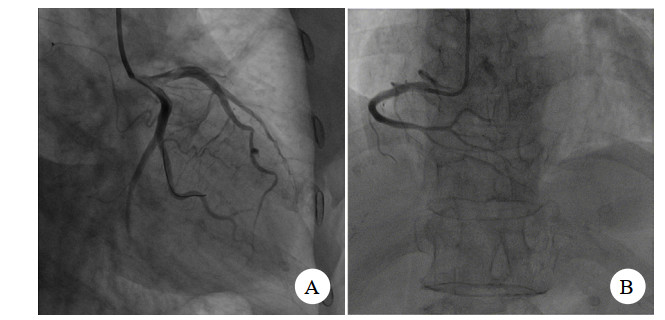

入院后考虑患者起病11 h,仍有胸痛,且心电图Ⅱ、Ⅲ、avF ST段上抬,故有急诊介入治疗手术指征,遂与患者家属交代病情,签署知情同意书后安排急诊介入手术。急诊介入过程见图 2、图 3。

| 图 3 痉挛解除后图像 |

患者冠脉造影提示:①前降支中远端弥漫狭窄80%~90%,第一对角支:全程弥漫狭窄70%~80%,前降支及对角支远端TIMI血流2~3级;前降支逆向有侧支循环提供;②回旋支:近端狭窄85%,回旋支中段闭塞,钝缘支近端闭塞,TIMI血流0级;③右冠状动脉:中段以远闭塞,TIMI血流0级。考虑三支冠脉严脉痉挛。术中予去甲肾上腺素维持下予冠脉内注射硝酸甘油,硝普纳后患者冠脉痉挛解除,冠脉内注入尿激酶原20 mg抗栓,经处理后患者冠脉痉挛解除。